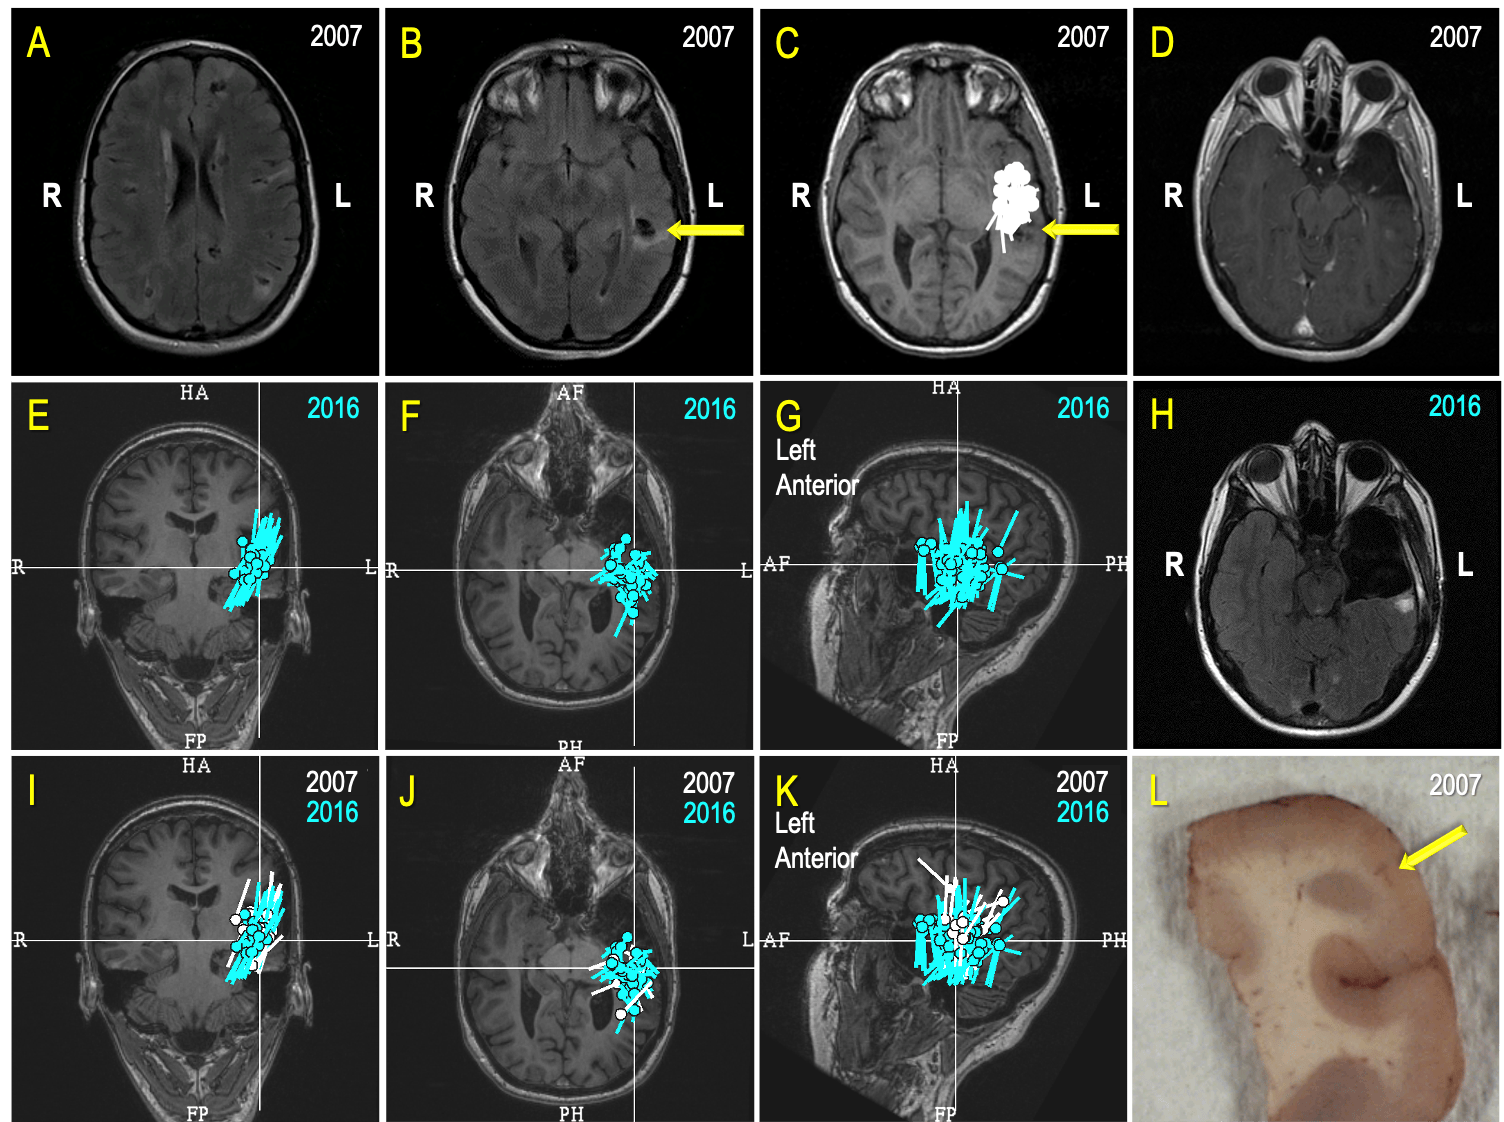

Figure 7. A Case Review (A-L): A 26-year-old college graduate began experiencing seizures a few times a week 10 years prior (at age 16) as she was about to acquire a driver’s license. The patient failed several antiseizure medications (ASMs) and aged out of pediatric care at UPMC Children's. An operation to cure her epilepsy was her constant desire, but the prospect of surgery was a very challenging and risky proposition because she has a multifocal disease – Tuberous sclerosis (A, B). After a comprehensive evaluation, a MEG greatly simplified planning for an invasive monitoring by revealing a seizure focus close to a left temporal, partially calcified tuber (C, yellow arrow on B, C & D; 2007). Ultimately, a possible degree of the left anterior temporal resection, limited by the language functions close to the tuber (D; 2007), led to seizure freedom and "new, great life.” Unfortunately for this patient, seven years later, in 2014, she again began to have seizures. A new set of investigations, including a MEG, revealed “a cluster” indicative of an active seizure focus in the “same area” as before (E, F, G). The patient underwent a modern type of invasive monitoring (stereo-EEG) planned around her MEG findings. She ultimately had a more extensive left temporal surgery (H). In preparation for a multidisciplinary patient management discussion, our team displayed the MEG results from 2007 (white) and 2016 (turquoise) on the same MRI (I, J, K) and established that there was significant overlap. As epileptologists, our team inferred that the patient’s original surgery did not remove the seizure focus but instead only interrupted its manifesting network. While this surgery led to seven years of freedom from seizures, and to quote the patient, a “new, great life," it became apparent that a more complete resection would be necessary to give the patient another opportunity at a seizure-free life. Histopathologic findings within the resected specimen (L) from the second surgery revealed cortical development malformation with Balloon Cells and Rosenthall fibers. The patient experienced occasional seizures during the first year following her second surgery, but she is now enjoying the fourth year of a new seizure-free era. Thus, an accountable and competent incorporation of MEG in the comprehensive multidisciplinary evaluation and treatment of this patient directly contributed to rescuing at least 10 years of this young life from disabling seizures.